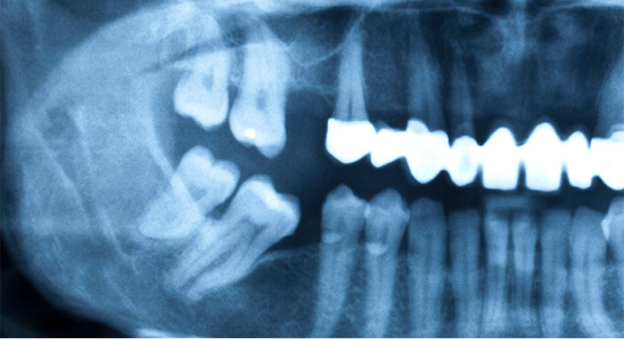

• 도미노 현상

치아가 상실된 경우 인접 치아가 비어있는 공간으로 쓰러지는 도미노 현상 이 나타날 수 있습니다.

• 부정교합

교합이 어긋나면서 턱관절 통증이 유발 될 수 있습니다.